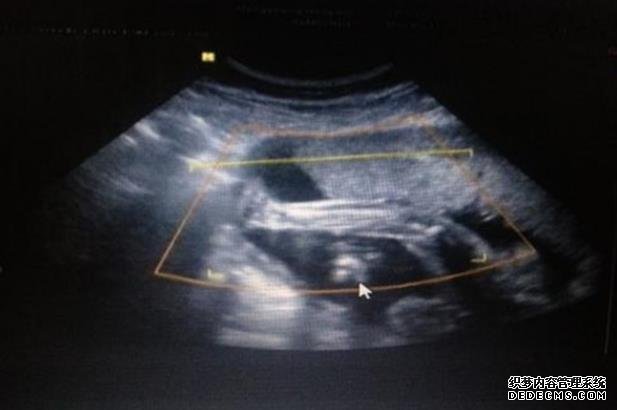

北京能做试管医院有几家 北京妇产医院待产包 ‘三维B超数据怎么看男女’